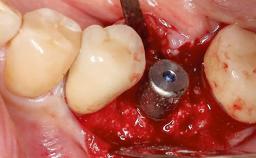

Treatment of Peri-Implantitis at a Zirconia Implant

Due to their promising clinical performance, zirconia implants have recently become popular alternatives to titanium implants, particularly for areas with high esthetic demands (Holländer and coworkers 2016; Roehling and coworkers 2016; Lorenz and coworkers 2019). However, regardless of the reported high survival and success rates, zirconia implants were affected by peri-implant diseases over the short observation period, suggesting the importance of treating peri-implant diseases at zirconia implants (Becker and coworkers 2017). In their case, Frank Schwarz and Ausra Ramanauskaite present 3-year results following mechanical debridement alongside Er:YAG laser monotherapy.